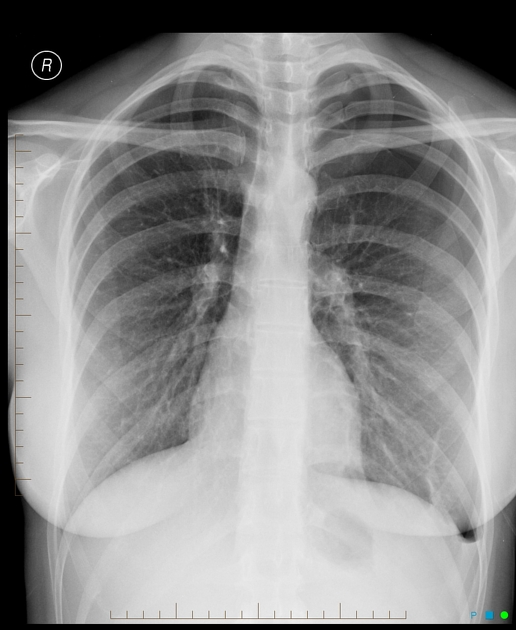

Describe the abnormality demonstrated.

Left-sided pneumothorax and left-sided pleural effusion (costophrenic blunting).